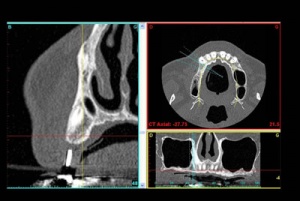

C'est la position spatiale de l'implant qui détermine la qualité de la prothèse en terme fonctionnel, esthétique.

Photos extraites du diaporama :